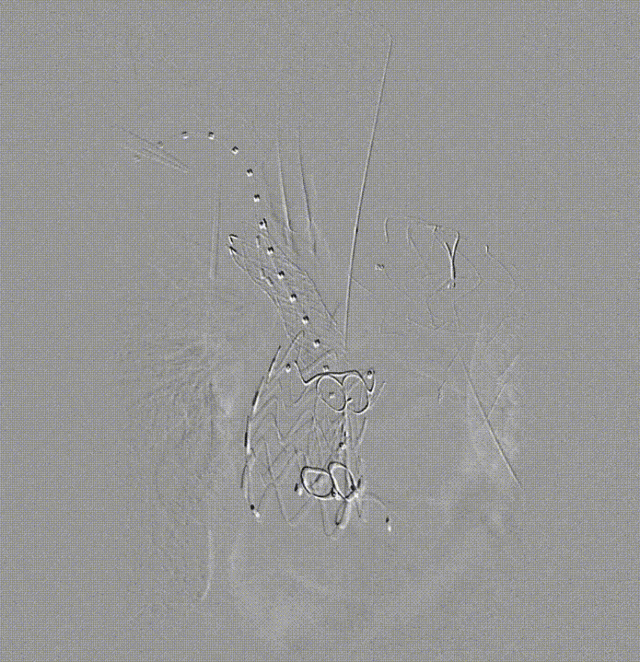

④ 术后造影

造影显示整体支架位置理想,弓上三分支血流通畅,无造影剂滞留,无夹层,假腔内漏完全消失。

远端造影可见内脏动脉区存在破口,且有逆向造影剂流动。本次手术暂未处理,后续将进一步探讨治疗方案。

术后复查

术后一周 CT 复查结果令人满意,整个支架形态良好,三分支通畅,Ia 型内漏完全消失,胸主动脉上段基本血栓化。因为内脏区域破口的存在,胸主动脉远端假腔仍有造影剂痕迹,但这并不影响整体手术效果。